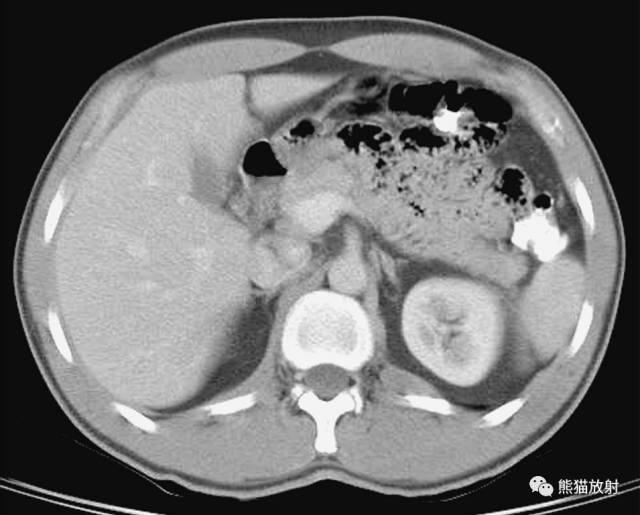

第三层

1、肝右叶;2、肝尾状叶;3、下腔静脉;4、肝门静脉;5、腹直肌;6、肝圆韧带;7、肝左叶;8、十二指肠降段;9、腹白线;10、肠系膜上动脉;11、腹腔干;12、胃;13、脾静脉;14、胰腺;15;空肠;16、横结肠;17、降结肠;18、左结肠静脉;19、腹外斜肌;20、膈肌;21、奇静脉;22、髂肋肌(胸段);23、胸导管;24、胸椎;25、棘肌;26、椎管和脊髓;27、腹主动脉;28、半奇静脉;29、最长肌;30、肾上腺动脉;31、左侧肾上腺;32、左肾;33、左肺;34、背阔肌;35、脾脏;36、肝门区;37、圆韧带凹痕;38、肝十二指肠韧带;39、网膜孔;40、网膜囊/大网膜;41、胰淋巴结;42、右膈下隐窝;43、肝淋巴结;44、腰淋巴结;45、膈上淋巴结;46、后纵隔;47、脾门;48、左结肠旁沟。